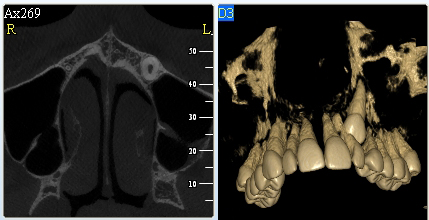

3D DVT - NewTom

Je speciální zubní digitální tříprostorový tomograf (3D), který umožňuje na základě jediného

snímkování vytvořit všechny typy RTG zobrazení, které jsou pro lékaře potřebné. Díky používané technologii tzv. „kuželového paprsku“ a speciálním senzorům je

výrazně zmenšená dávka záření - o více jak 80% proti klasickému CT vyšetření. To je významné zejména u dětí. Pomocí tohoto přístroje je možné zjisti skutečnou situaci v čelistních kostech pacienta tedy množství kosti - můžeme změřit skutečnou šířku i výšku kosti, i kvalitu kosti (hustotu) v místě uvažované implantace. 3D (tříprostorové) zobrazení umožňuje zvýšit prostorovou představu operatéra ještě před vlastní operací a zároveň pacientovi lépe objasnit a ukázat oblast plánovaného zavedení implantátu.

Pacient „neumí číst“ RTG snímky, ale díky 3D zobrazení vidí „svoji skutečnou čelist“

- např. jak je nízká či úzká, vidí průběh nervu nebo velikost čelistní dutiny, což mu umožní i pochopení nutnosti v některých případech provést pomocné zákroky ještě před vlastním zavedením implantátu (viz. kostní štěp, sinus lift, kostní granulát...).

Vyšetření pomocí tohoto přístroje používáme i ve stomatochirurgii (zlomeniny čelistí, zuby moudrosti, cysty, onemocnění čelistního kloubu), ortodoncii (retinované zuby, nadpočetné zuby), parodontologii atd.

NewTom Giano

Jedná se o nejnovějším přístroj ze skupiny dentálních hybridních CBCT (3D) + 2D (pan i ceph) systémů. Opět umožňuje na základě jediného snímkování vytvořit všechny typy RTG zobrazení, které jsou pro lékaře potřebné. Používaná technologii tzv. „kuželového paprsku“ a speciální senzory pro minimální zátěž při snímkování pacienta.

Vyšetření pomocí tohoto přístroje (nebo

3D DVT - NewTom) a získaná data používáme

pro každou implantaci, dále ve stomatochirurgii (zlomeniny čelistí, zuby moudrosti, cysty, onemocnění čelistního kloubu), ortodoncii (retinované zuby, nadpočetné zuby), parodontologii atd.